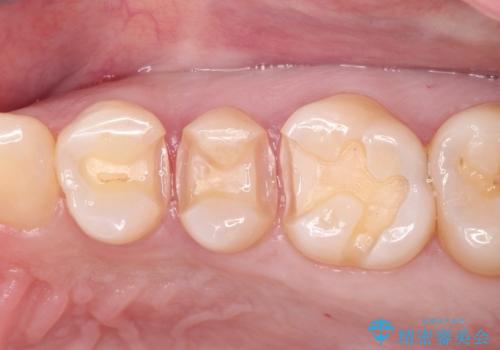

古い材料を除去すると中で虫歯が進行していたため、顕微鏡下で虫歯を除去した後セラミックインレー、PGAインレーにて修復治療を行いました。

すべての処置で拡大鏡及び顕微鏡を用いるため高い精度で治療を行うことができます。